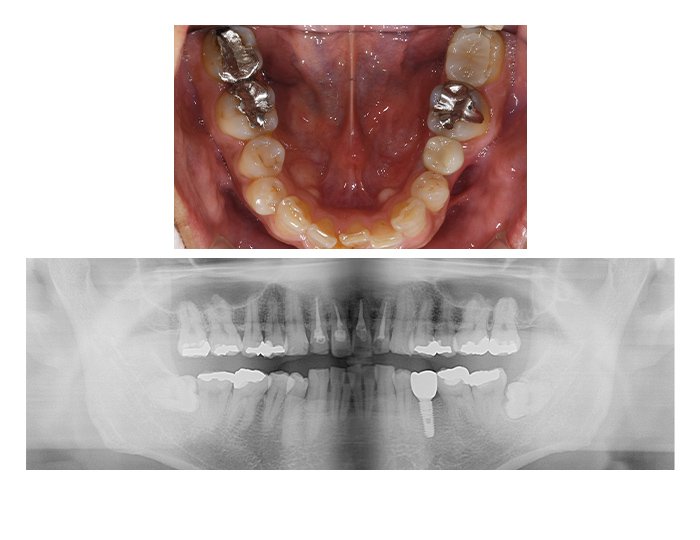

症例02 奥歯のインプラントと骨造成(男性、期間9カ月)

BEFORE(術前)

AFTER(術後)